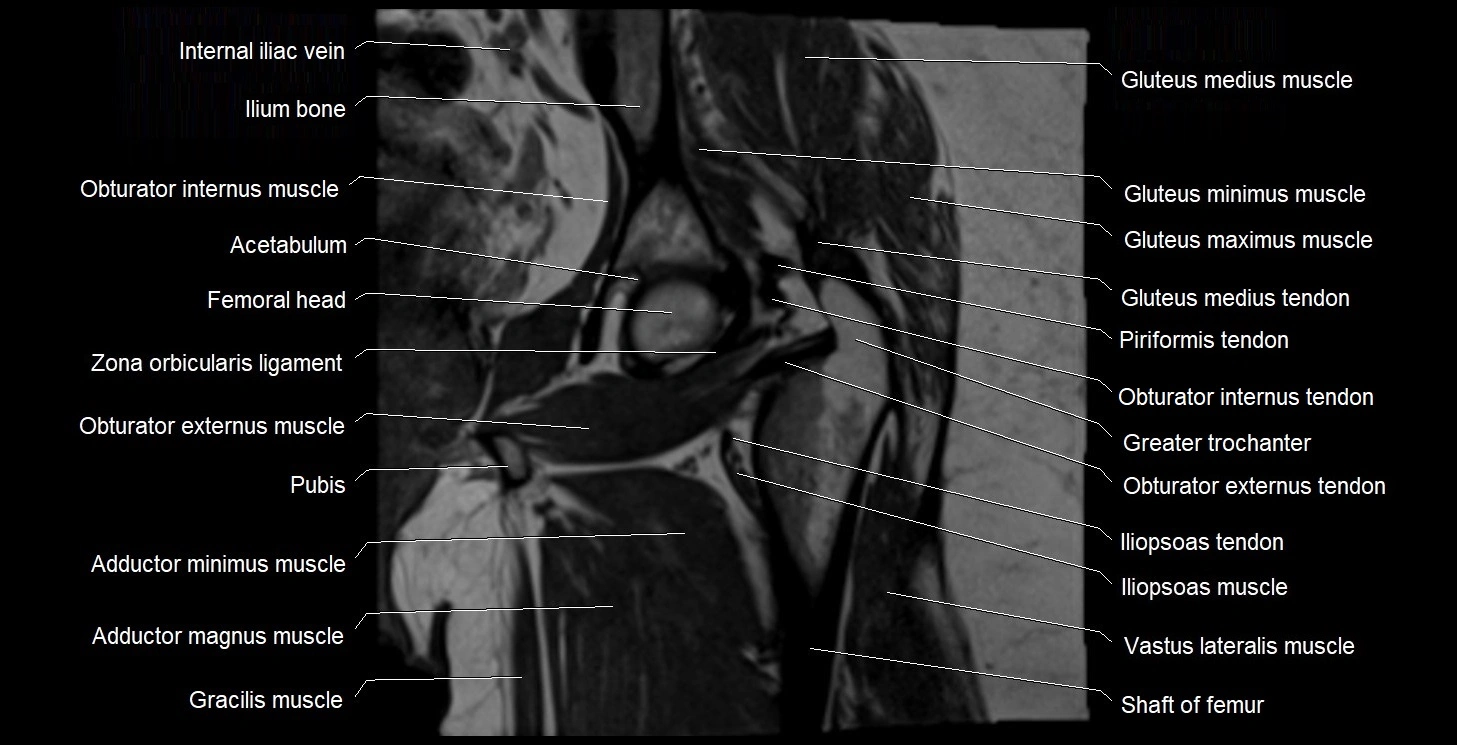

- Acetabulum

- Ala of sacrum

- Body of ilium

- Gracilis muscle

- Greater trochanter

- Head of femur

- Iliopsoas muscle

- Iliopsoas tendon

- Ilium bone

- Obturator externus muscle

- Obturator externus tendon

- Obturator internus muscle

- Obturator internus tendon

- Pectineus muscle

- Gluteus medius muscle

- Gluteus medius tendon

- Gluteus minimus muscle

- Gluteus minimus tendon

- Gluteus maximus muscle

- Zona orbicularis ligament